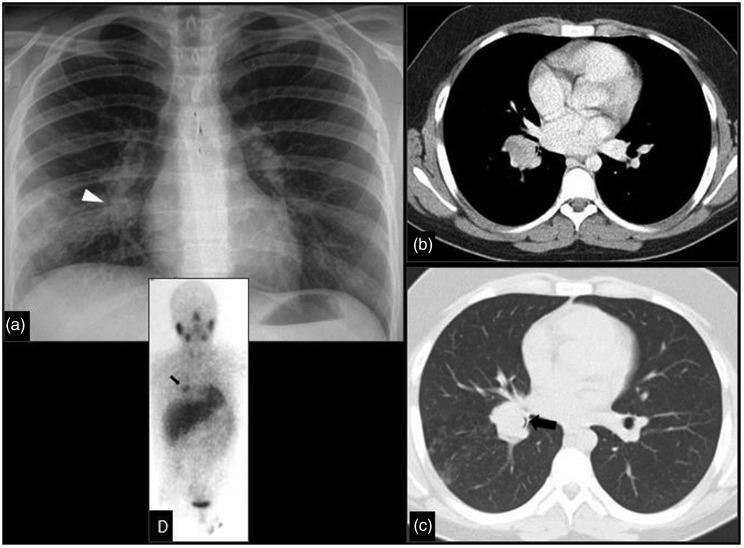

The purpose of this current pictorial review is to define the solitary round pulmonary lesion (SRPL), to familiarize with its prevalence in the pediatric population, and, moreover, to educate radiologists on its vast differential diagnosis and imaging manifestations. Furthermore, by highlighting valuable clues, it intends to assist radiologists efficiently partake in its diagnosis, work-up, and follow-up in order to narrow down the differential diagnosis by working alongside the clinician and combining clinical information, lab results, and radiological findings.

本次影像综述的目的是明确孤立性圆形肺病变(SRPL),使其在儿科人群中的患病率,此外,使放射科医生熟悉其广泛的鉴别诊断和影像学表现。此外,通过强调有价值的线索,旨在帮助放射科医生有效地参与其诊断、检查和随访,以便通过与临床医生合作并结合临床信息、实验室结果和影像学发现来缩小鉴别诊断范围。